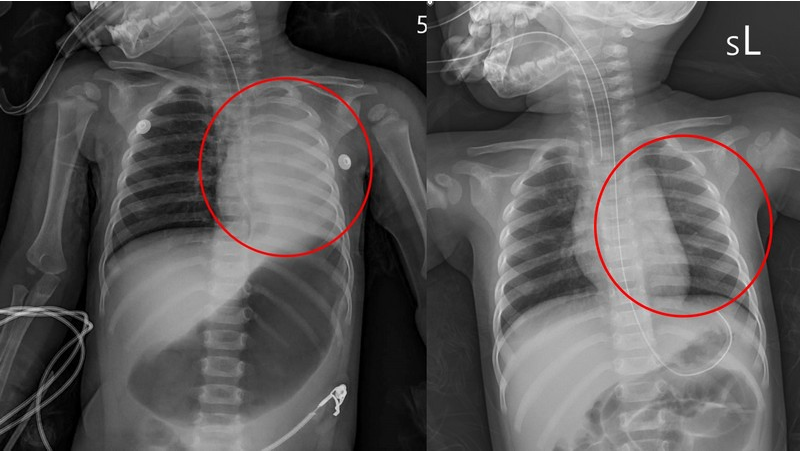

左圖:X光影像顯示孩子的左邊肺部已經呈現白色塌陷狀態。

右圖:將異物取出後氧氣進入,孩子的左肺部不再塌陷,恢復正常充氣狀態。

不滿一歲的小佩(化名)抵達花蓮慈院急診室時,已有明顯膚色變暗、意識不清且身體些微抽搐等缺氧症狀,為避免孩子持續缺氧造成身體損傷,當時在急診值班的兒科病房主任陳明群很快地幫她放入氣管內管,讓肺部能夠獲得足夠的氧氣,並立刻安排進行X光檢查,發現小佩的左邊肺部已經呈現白色塌陷狀態,而右肺部則有過度充氣的現象,團隊進一步做電腦斷層排查原因,找到了原因就是卡在左支氣管入口的異物。小佩很快的從急診轉往兒童加護病房,在初步解決危急情況後,醫療團隊於當日上午利用支氣管鏡檢查,將異物取出,發現這個奪走孩子呼吸的東西,是長3.5公分、寬0.5公分的硬式隱形眼鏡吸棒,所幸把吸棒拿出來後,小佩的恢復情況良好,在二十一日順利出院返家。